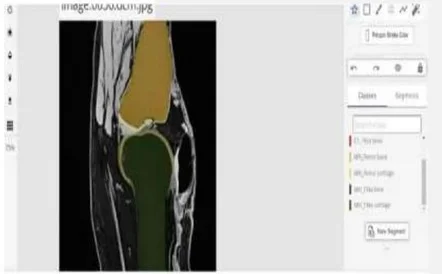

MR Annotations

Image collections